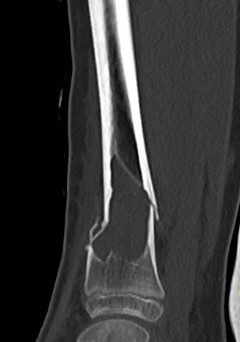

X-ray

Well-defined lucency

- thin sclerotic rim

- usually central

- thinned cortex with slight expansion

- thin internal septa

- can be multi-loculated

Fallen-Leaf (AKA fallen-fragment)

- with pathological fracture

- indicates that the lesion has no matrix and is fluid filled

Fallen leaf sign

DDx ABC

ABC

- eccentric (v central)

- width > physis

- can be very difficult to tell

- requires biopsy